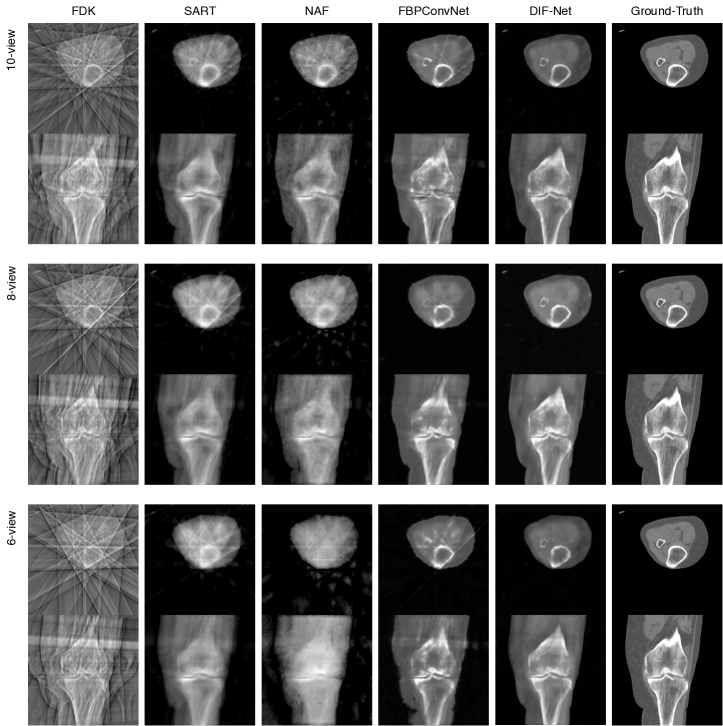

Refer to caption

Figure 3: Qualitative comparison of 10-view reconstruction.

Performance. As shown in Table 1, we compare DIF-Net with four previous methods [1, 6, 22, 29] under the setting of reconstruction with different output resolutions (i.e., 1283,2563superscript1283superscript2563128^{3},256^{3}) and from different numbers of projection views (i.e., 6, 8, and 10). Experiments show that our proposed DIF-Net can reconstruct CBCT with high image quality even using only 6 projection views, which significantly outperforms previous works in terms of PSNR and SSIM values. More importantly, DIF-Net can be directly applied to reconstruct CT images with different output resolutions without the need for model retraining or modification. As visual results are shown in Figure 3, FDK [6] produces results with many streaking artifacts due to lack of sufficient projection views; SART [1] and NAF [29] produce results with good shape contours but lack detailed internal information; FBPConvNet [11] reconstructs good shapes and moderate details, but there are still some streaking artifacts remaining; our proposed DIF-Net can reconstruct high-quality CT with better shape contour, clearer internal information, and fewer artifacts. More visual comparisons of the number of input views are given in the supplementary material.